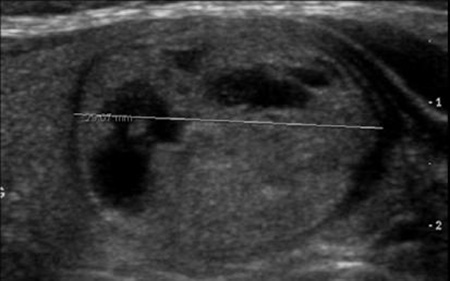

Ultraschall - regressiv-cystischer Knoten ohne Krebsverdacht

Liegt ein kalter Knoten vor, so muss abgeklärt werden, ob es sich um einen "harmlosen" Knoten handelt oder ob Verdacht auf Schilddrüsenkrebs besteht. Neben der Szintigraphie ist heute primär der Ultraschall (Sonographie) die wichtigste Untersuchung zur Abklärung und Einschätzung von Knoten. "Echoreiche" und gut abgrenzbare Knoten deuten auf gutartigen Charakter hin harte, echoarme und schlecht abgrenzbare Adenome sind eher kritische Zeichen ebenso Knoten mit Mikrokalk, vor allem, wenn dasselbe Ultraschallmuster auch in Lymphknoten vorliegt. Metastasen in Lymphknoten zeigen häufig dasselbe Gewebebild.